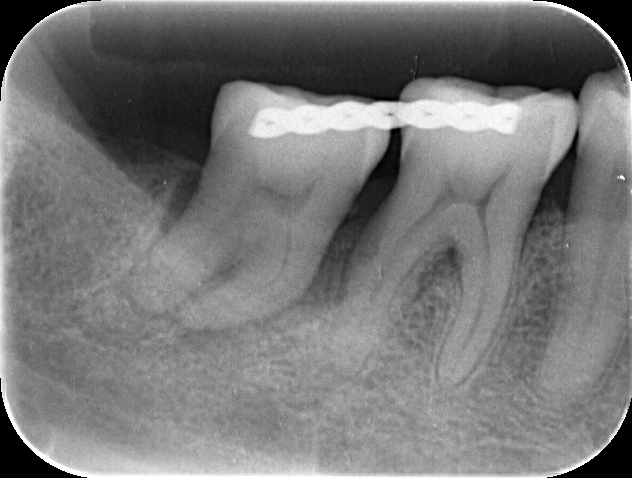

写真の方は、奥から2番目の歯(第2大臼歯)の歯周病がかなり進行してしまい、歯がグラグラして、痛くて噛めないということで来院されました。

可能な限り歯の保存に努めますが、重度の根分岐部病変も認められ、歯周病治療を行っても改善は困難と判断し、抜歯をすることを提案させていただきました。

そして、下の写真のように、抜歯した親知らずを移植し、安静を図るため手前の歯と固定しました。

移植後3〜4週で、根完成歯の場合には根管治療を始めます。

今回は、根管治療後、ジルコニアクラウンを装着しました。写真は、治療が終了したところです。